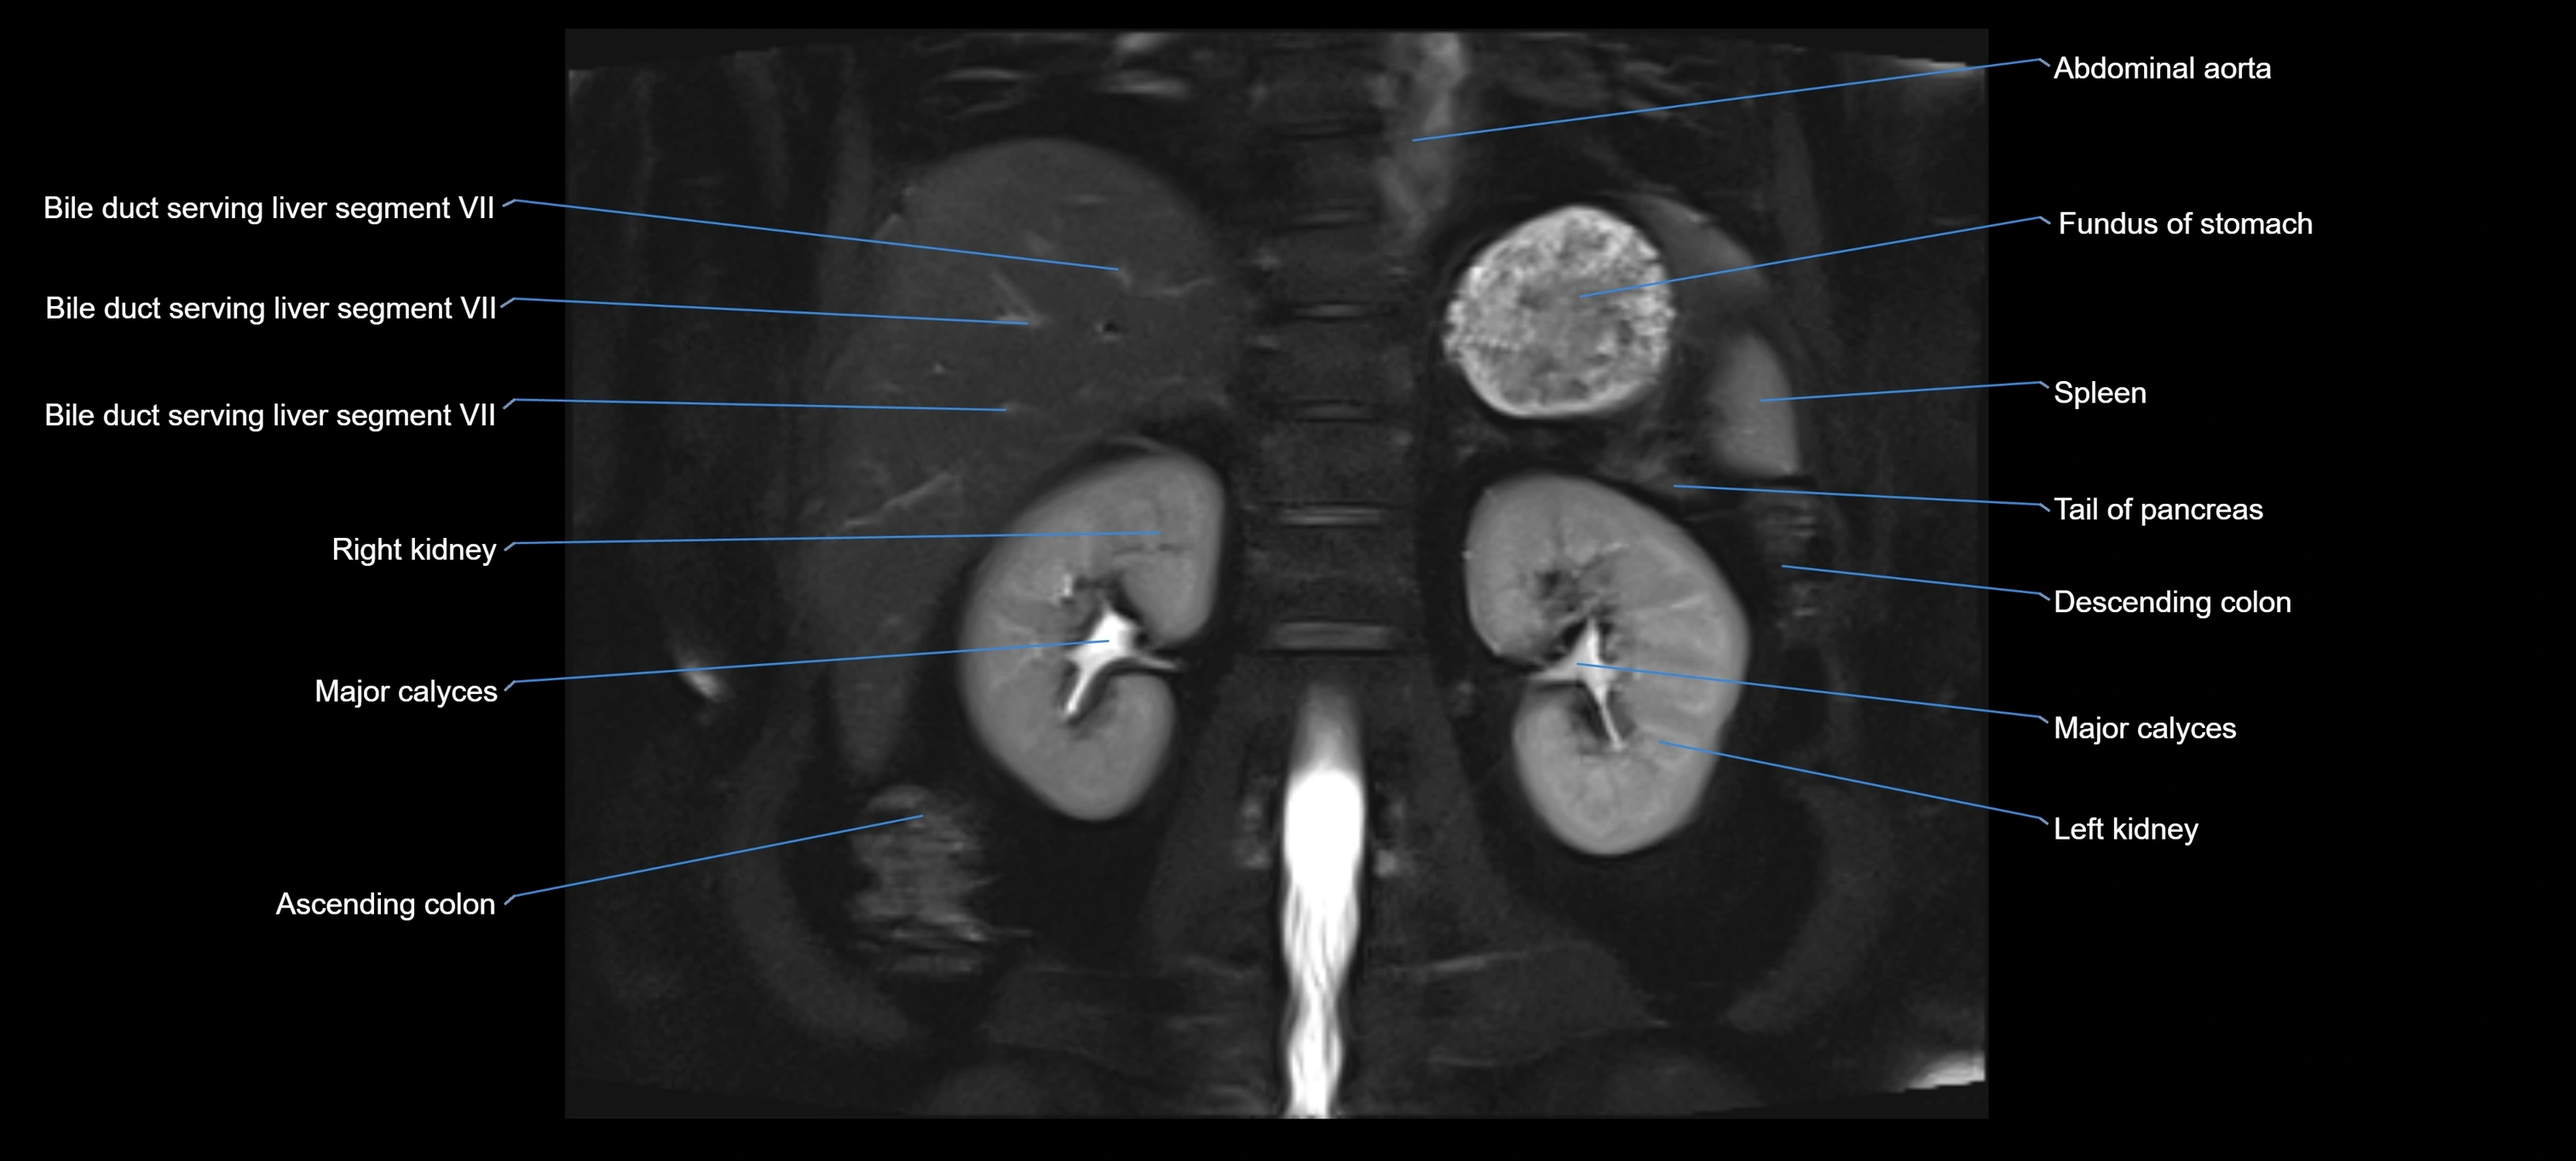

MRI image

image

Fullscreen Image